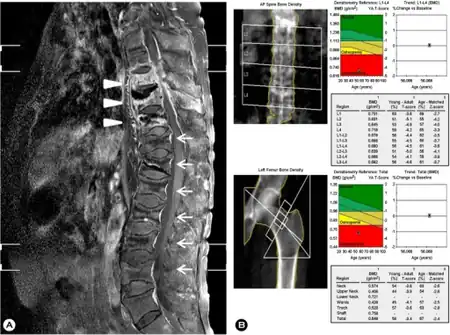

| a) MRI of spine - spondylitis of T8, 9, 10 and subligamentous abscesses arrow b) Low bone mineral density at lumbar spine/femur | |